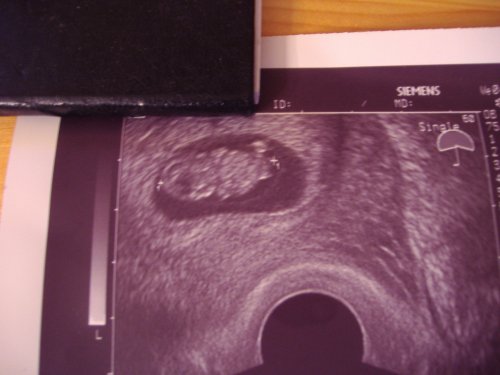

Kata, tündéri a képen a babód!!! Én ma megyek, a napokból próbálok következtetni, h akkor már nekem is jól látható lesz a kis gubacsom:D